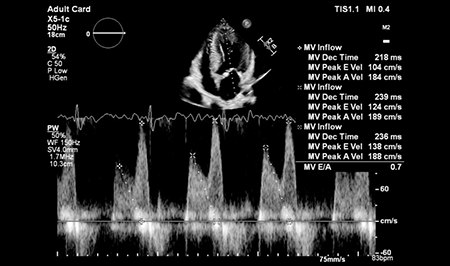

Reconnaissance automatique des incidences, placement automatique du contour, suivi du Speckle, cet outil permet une mesure GLS robuste et reproductible en un seul clic.